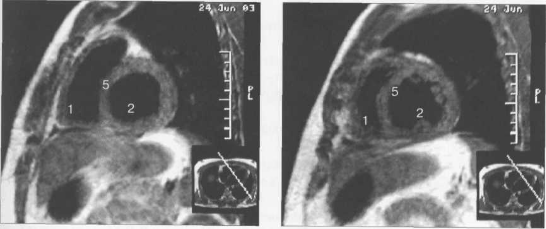

МРТ позволяет получать изображения сердца в поперечной (аксиальной), фронтальной (корональной) и сагиттальной плоскостях (ортогональные сечения). Поскольку анатомические оси сердца и магистральных сосудов (за исключением аорты в нисходящем отделе и полых вен) не совпадают со стандартными ортогональными плоскостями исследования, общепринятыми при исследованиях других органов и систем организма, для МРТ-исследования сердечно-сосудистой системы разработаны дополнительные наклонные срезы (двухкамерное сечение, четырехкамерное сечение, сечение по короткой оси левого желудочка).

Рис. 9.47. МРТ сердца. Аксиальная плоскость.

Здесь и на рис. 9.48—9.52:

I — правый желудочек, 2 — левый желудочек, 3 — правое предсердие, 4 — левое предсердие, 5 — межжелудочковая перегородка, 6 — межпредсердная перегородка, 7 — задняя стенка левого желудочка, 8 — восходящая часть аорты, 9 — дуга аорты, 10 — нисходящая часть аорты, 11 — легочный ствол, 12 — правая легочная артерия. 13 — левая легочная артерия, 14 — верхняя полая вена, 15 — нижняя полая вена, 16 — трахея.

Рис. 9.49. МРТ сердца. Двухкамерные сечения.

Рис. 9.51. МРТ сердца. Сечения по короткой оси левого желудочка.

Рис. 9.52. МРТ сердца. Четырехкамерные сечения.

На рис. 9.47—9.52 представлены Т1-ВИ наиболее часто используемых МР-сечений сердца.